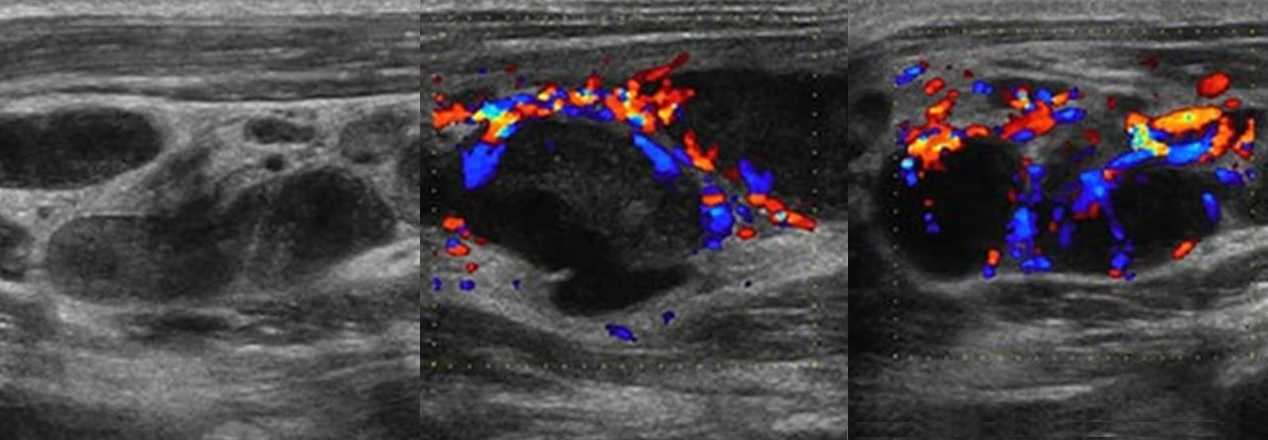

Подмышечная лимфаденопатия сопровождает целый ряд заболеваний молочных желез: фиброзно-кистозную, диффузно-узловую мастопатию, фиброму, липому, рак груди. УЗИ позволяет наилучшим образом оценить дифференцировку корковой и центральной частей узлов, выбрать узел для биопсии. Чаще всего пользуются УЗИ с цветным картированием. Возможна эластография, оценивающая плотность разных участков лимфатического узла.

Метастазы рака молочной железы в поверхностных лимфоузлах